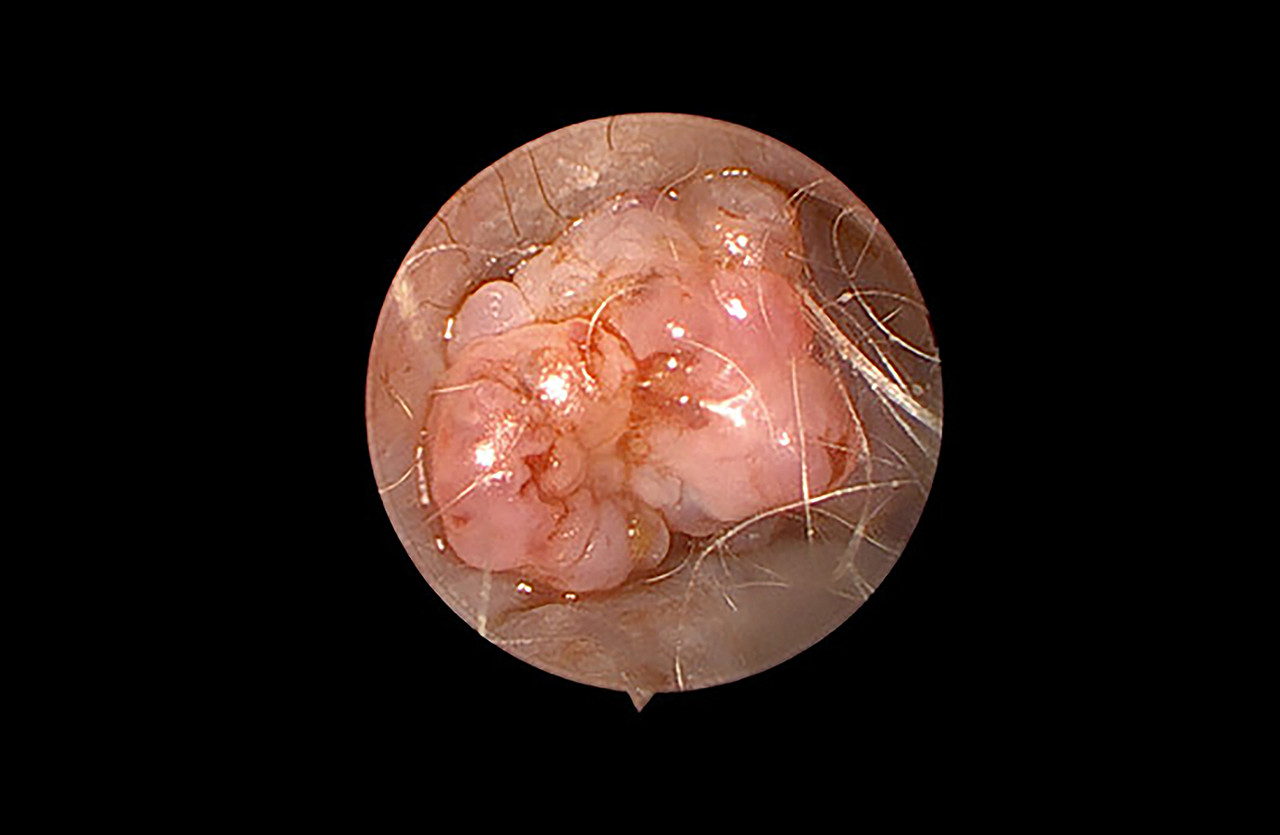

내시경

외부 절개 없이 체내에 고화질 내시경 카메라를 삽입 필요한 수술과 검사를 할 수 있습니다.

내시경 진료 중에는 움직임을 최소화해야 하기 때문에 마취가 필요할 수 있습니다.

안정된 후 체내에 내시경을 삽입하여 실시간으로 영상을 확인하며 필요한 수술 및 검사가 진행됩니다.

위/식도 이물 제거, 위/십이지장 조직검사, 폴립 제거, 대장 검사, 조직검사

이도(귀) 검사, 폴립 제거

비강(코) 검사, 비강내 이물 제거, 비강 조직검사

기관/기관지 검사, 기관/기관지 이물 제거